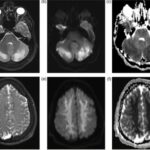

Se pueden mencionar al respecto los estudios que han encontrado en pacientes dependientes al alcohol una disminución del volumen de sustancia gris en el área de la corteza frontal, el hipocampo y el tálamo. El volumen de las sustancias blanca y gris también se puede ver disminuido en el área periventricular, la protuberancia y el cerebelo. Estos déficits de volumen también se han localizado en la corteza prefrontal dorsolateral derecha, ínsula anterior derecha, en el núcleo accumbens y en la amígdala izquierda(16) (ver Imagen 1).

Asimismo, como se indicó previamente, a través de la TC también se puede observar el deterioro de la microestructura cerebral por adicción al alcohol. El abuso de esta sustancia altera cinco fibras del cerebro, como el cuerpo calloso, el fondo de saco, la cápsula externa, el cíngulo circunvolución y el fascículo longitudinal superior, las que están involucradas en funciones como el procesamiento visoespacial y del lenguaje, la comunicación interhemisférica, la memoria, el procesamiento emocional, la toma de decisiones y la integración sensorial(16) (ver Imagen 2).